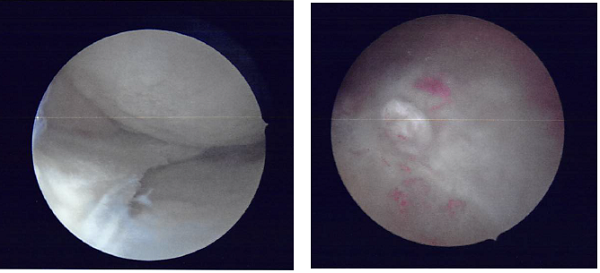

I performed a partial meniscectomy using a shaver as well as straight and upbitters. A balanced margin was reached. Following that the shaver was moved to the intercondylar notch where the cyclops excision was performed using the shaver.

The shaver and the arthroscope was moved to the lateral compartment where partial meniscectomy of the medial frayed margins of the lateral meniscus was performed using the shaver. Chondroplasty of the medial tibial condyle as well as chondroplasty of the trochlea was performed using the shaver.